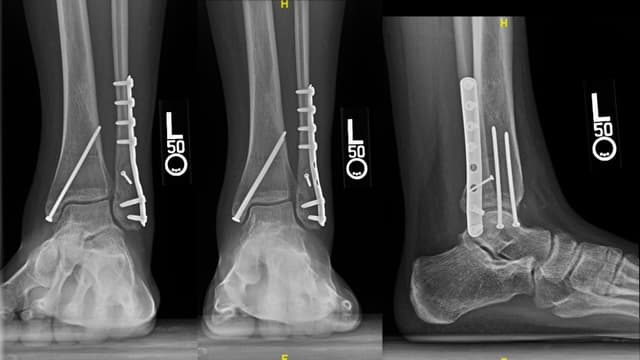

Imaging

Post-op